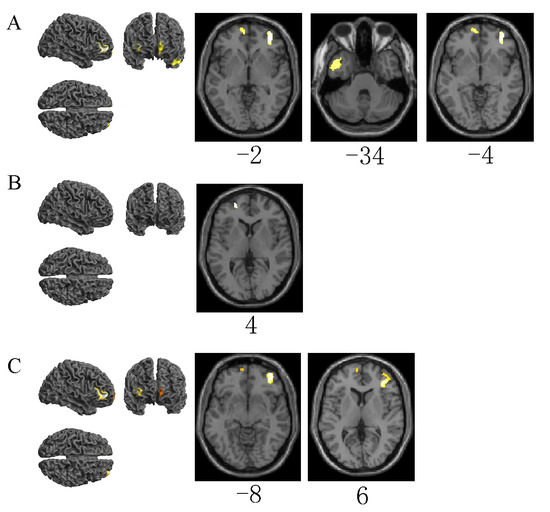

3.3. Differences in Brain Area Activation between Distracted and Normal Driving Emergency Braking

| Emergency braking (visual distraction driving vs. normal driving) | 36 | 50 | −2 | 384 | 4.62 | R | Middle frontal gyrus, orbital part |

| −42 | 4 | −34 | 290 | 3.93 | L | Inferior temporal gyrus | |

| −6 | 60 | −4 | 171 | 3.85 | L | Middle frontal gyrus, orbital part | |

| Emergency braking (auditory distraction driving vs. normal driving) | −22 | 54 | 4 | 52 | 3.54 | L | Superior frontal gyrus, dorsolateral |

| Emergency braking (cognitive distraction driving vs. normal driving) | 40 | 52 | −8 | 558 | 5.91 | R | Middle frontal gyrus, orbital part |

| −6 | 62 | 6 | 89 | 3.70 | L | Superior frontal gyrus, medial | |